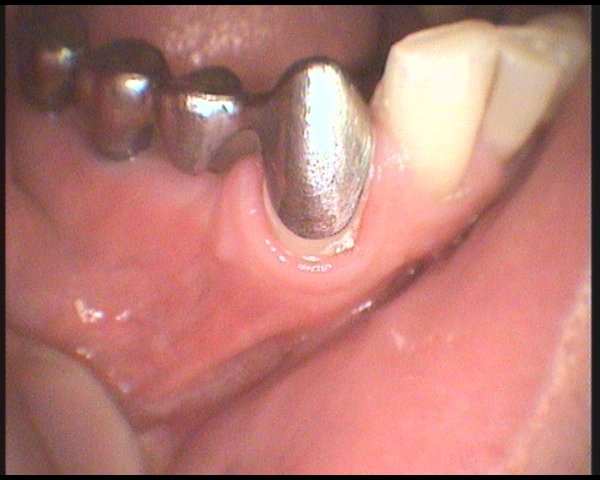

KorunkaV okamžiku, kdy kaz zničil převážnou část zubu nebo došlo k výraznému oslabení korunky zubu, bývá vhodným ošetřením korunka. Korunku lze zhotovit pouze z kovu nebo kompozitního materiálu, nejčastěji se však jedná o kombinace kovu a keramiky (tzv.metalokeramická korunka). V dnešní době stoupá zájem o korunky zhotovené z čisté keramiky, které jsou dokonalé esteticky. Jsou však vhodnější pouze k náhradám menšího rozsahu. Volba vhodného typu korunky je otázkou priorit pacienta a dohody se zubním lékařem. Korunku je nutné čistit a pečovat o ni stejně jako vlastní zub.